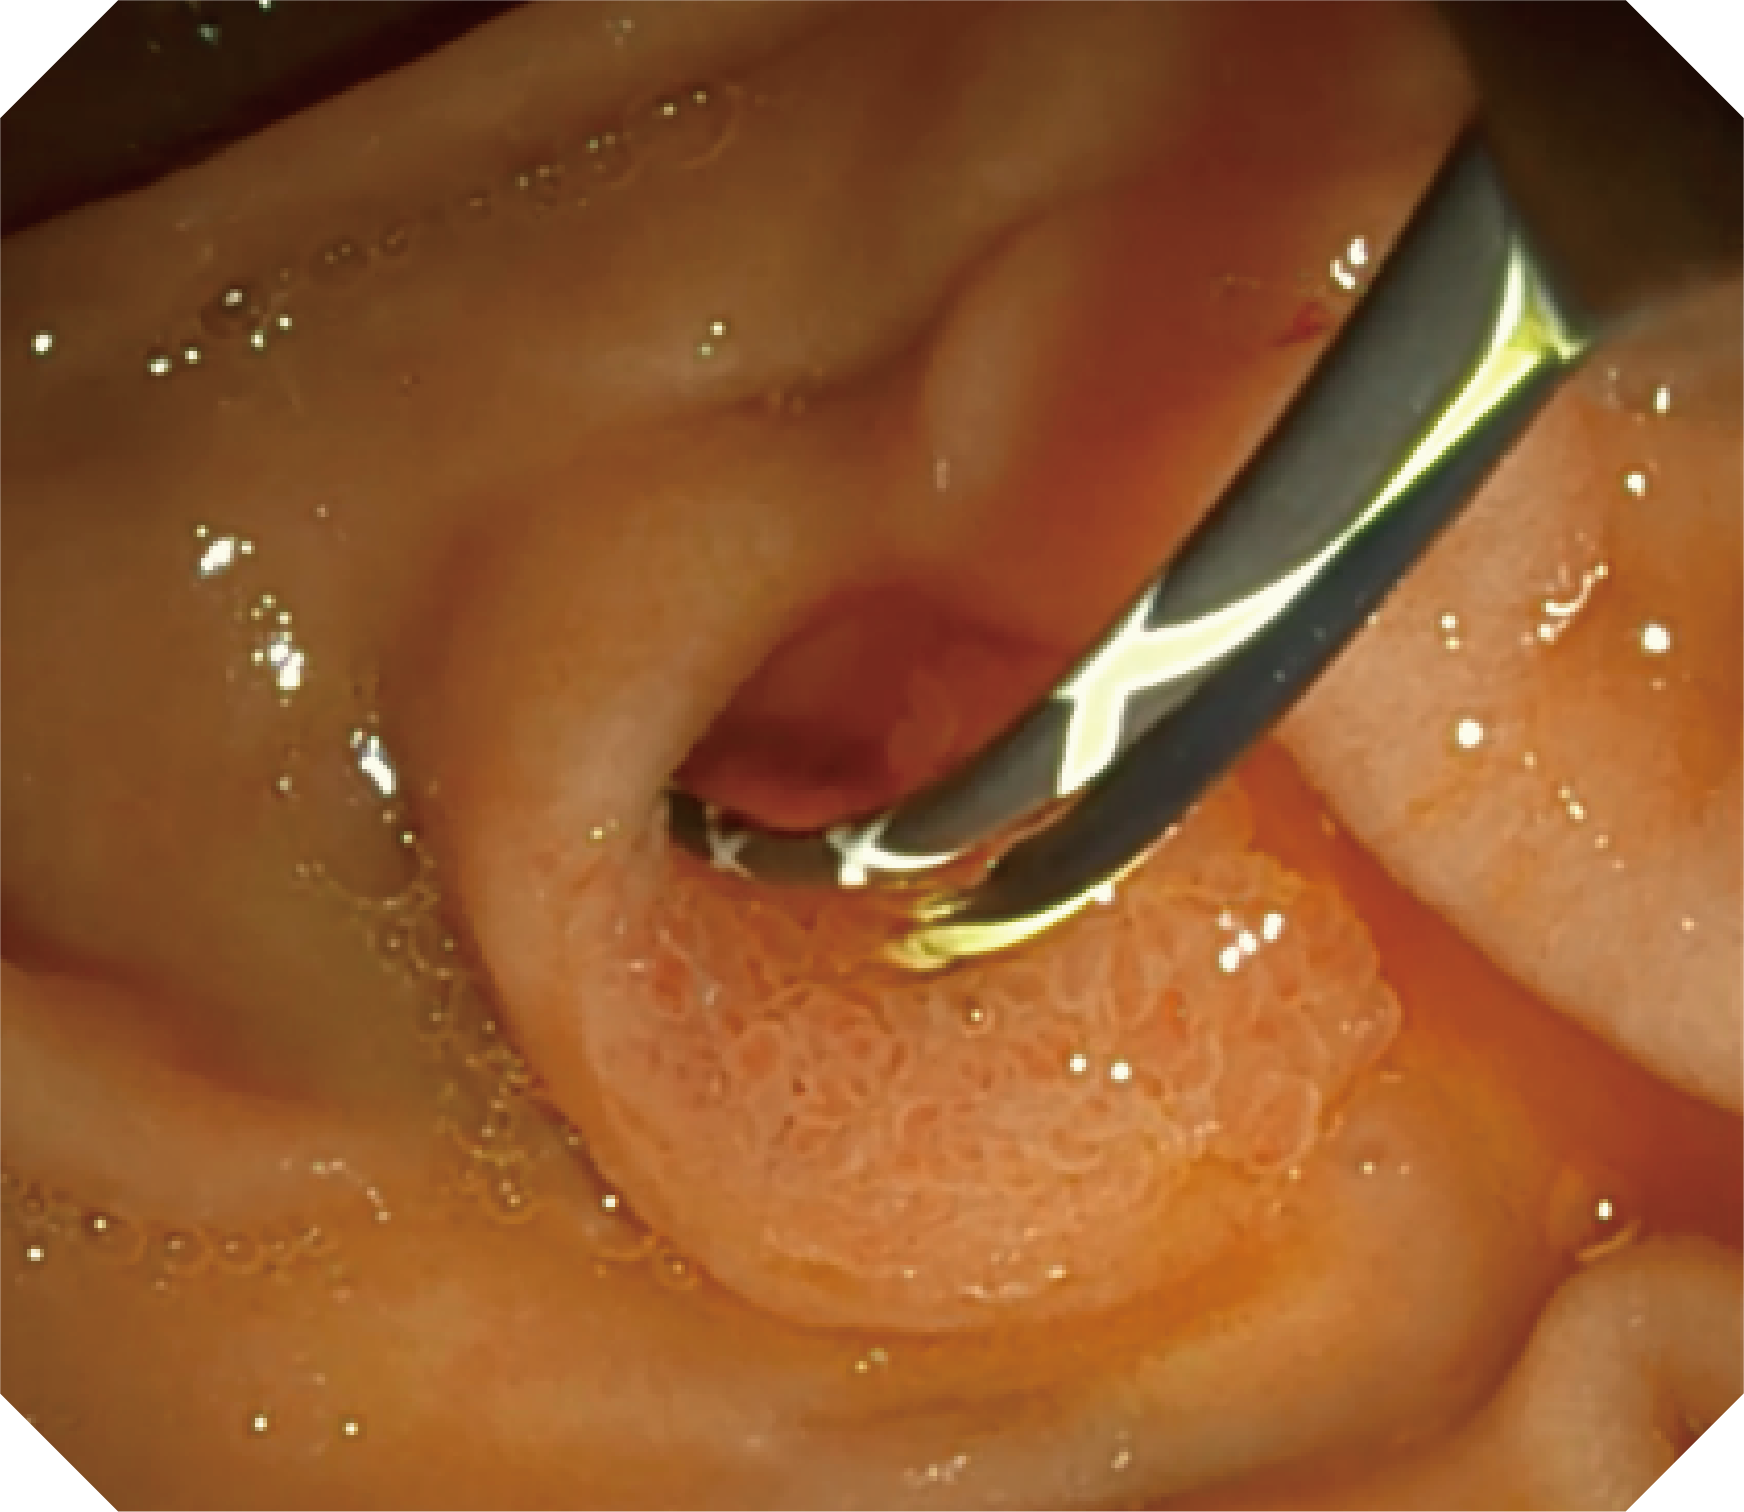

• 器械辅助导向功能

当切开刀伸出视野外时,导向面引导其回归视野